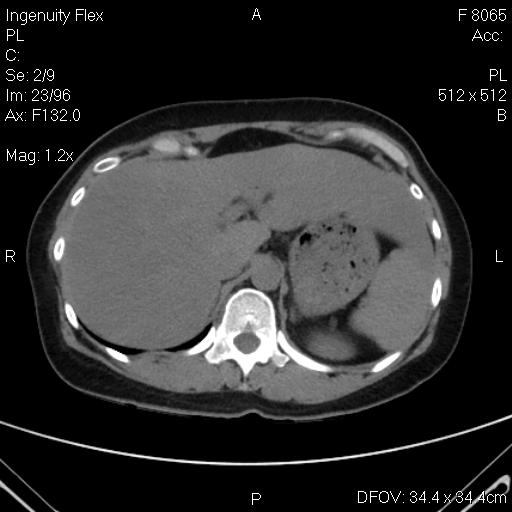

CT-bụng-hemagioma gan (P)

CT-bụng-ung thư bàng quang xâm lấn niệu quản

CT-ung thư vòm-di căn gan phổi